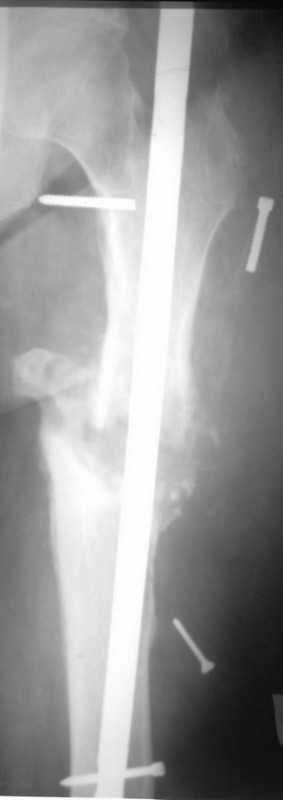

Здравствуйте уважаемые коллеги, прошу Вашего мнения относительно тактики лечения пациента М. 37 лет, рост 170 см. вес 140 кг. Анамнез: пострадал в рез. ДТП в 2004 году, лечился в одной из районных больниц гдебыл прооперирован DCP. в 2006 году перелом м/фиксатора с последующим реостеосинтезом стержнем Кюнчера без блокирования. в 2007 году перелом фиксатора после чего обратился в нашу клинику, где было произведено удаление гвоздя, БИОС L-360 mm D-12 mm с кортико-спонгиозной пластикой, в теч. 6-и мес. больной был под наблюдением динамизация ч-з 2 мес. после чего пациент исчез с поля зрения. Появился с жалобами на болезненность в месте перелома, укорочение ноги, в течении года поочередно в ягодичной области и н/3 бедра функционирующие свищи. На данный момент имеем свищ в н\3 бедра, укорочение ноги на 3 см, внешняя ротация.Произведена фистулография, взят посев из свищевого хода. Планируется: - Удаление м\фиксатора и всех винтов(за исключением проксимального) - I&D с рассверливанием до 16 мм. - кортикотомия, открытое устранение деформаций - БИОС стержнем L-360 mm D-12 mm с а.б. покрытием - бусы с ванкомицином в области свищей

Уважаемый Илья! Если я правильно понял, фистулография у Вас - вторая картинка, а ранки на первой фотографии в области нижних блокирующих винтов и приблизительно на уровне псевдоартроза. Хотелось бы уточнить, есть ли клинические проявления свища на уровне псевдоартроза, отделяемое и т. д. Это существенно влияет на план операции - если перелом неинфицирован,а инфекция только на уровне нижних блокирующих винтов, достаточно удалить конструкции, те, что доступны, не стоит гоняться за кончиками винтов, произвести остеосинтез по Илизарову (на уровне малого вертела стержни, конечно)с п о с т е п е нн о й коррекцией угловой и ротационной деформаций. Параллельно ревизовать место расположения нижнего блокирующего винта, рассверлить, почистить, дренировать.